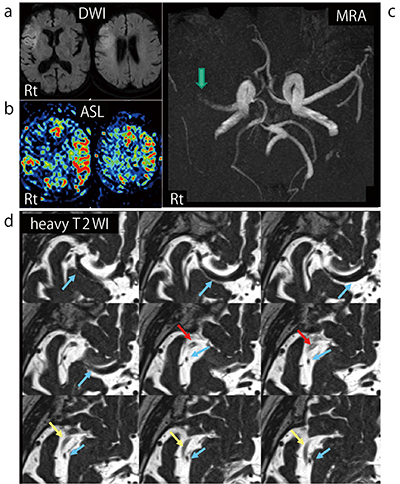

DWI,MRAにより急性脳血管閉塞を確認したところで,t-PAによる血栓溶解療法,血管内手術である血栓回収術の準備,家族への説明を進めながら,撮像を継続した(図1 a〜c)。3D-heavy T2WIでは,右内頸動脈から右中大脳動脈の分枝が陰性像として明瞭に描出されており,血管内の血栓と閉塞血管が正常血管より高信号に認められた(図1 d)。

図1 来院時DWI(a),ASL(b),MRA(c),3D-heavy T2WI(d)

右前頭葉に新しい梗塞巣を認め(a),同部より広い範囲で脳血流低下を認める(b)。MRA(c)では右中大脳動脈水平部に閉塞を認め(↓),3D-heavy T2WI(d)では開存している血管(→),閉塞部血栓(↓),閉塞後の血管(↓)を確認できる。